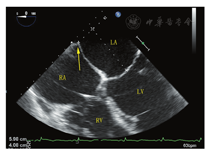

超声心动图在MR介入术中起着不可或缺的作用,下面以目前最为成熟的经导管二尖瓣夹合术MitralClip为例,阐述MR介入术中的超声评价。MitralClip是在TEE实时监测和引导下的操作,所有的导管操作由TEE监测和引导[16]。TEE首先引导房间隔穿刺,使得房间隔穿刺点距二尖瓣瓣环平面的高度3.5~4 cm(图11)。之后,TEE引导输送系统进入左心房并调弯、顶端垂直指向二尖瓣口。接着,TEE引导夹合器在二尖瓣上方定位,夹合器进入左心室,引导夹合器捕获和夹合瓣膜。夹合器捕获瓣膜位置,应该位于彩色多普勒显示反流束最大处。在整个手术过程中,两个超声切面非常重要,为手术的工作切面(X-plane双切面),包括三腔切面(左心室长轴切面)及二尖瓣交界处两腔切面(图12),前者可以显示二尖瓣A2、P2的位置,捕获瓣膜前二尖瓣夹合器应该在这个切面显示为"V"形,此时瓣夹合器臂与二尖瓣开放线垂直,分别位于A2、P2的位置,在该切面通过调整夹合器位置可使得夹合器更靠近前叶或后叶;后者显示P1,A2,P3,捕获瓣膜前二尖瓣夹合器在该平面应该为直线形,在该切面通过调整夹合器位置可使得夹合器更靠近内交界(3)或外交界(1)。另外一个工作切面为三维超声心动图的"二尖瓣外科视野",可以整体观察夹合器的位置、臂指向的方向(图13)。目前有限经验显示,经心尖二尖瓣夹合术(ValveClamp)术中超声指导和MitralClip总体上类似,但仍有部分差异,其超声规范尚在探索中。